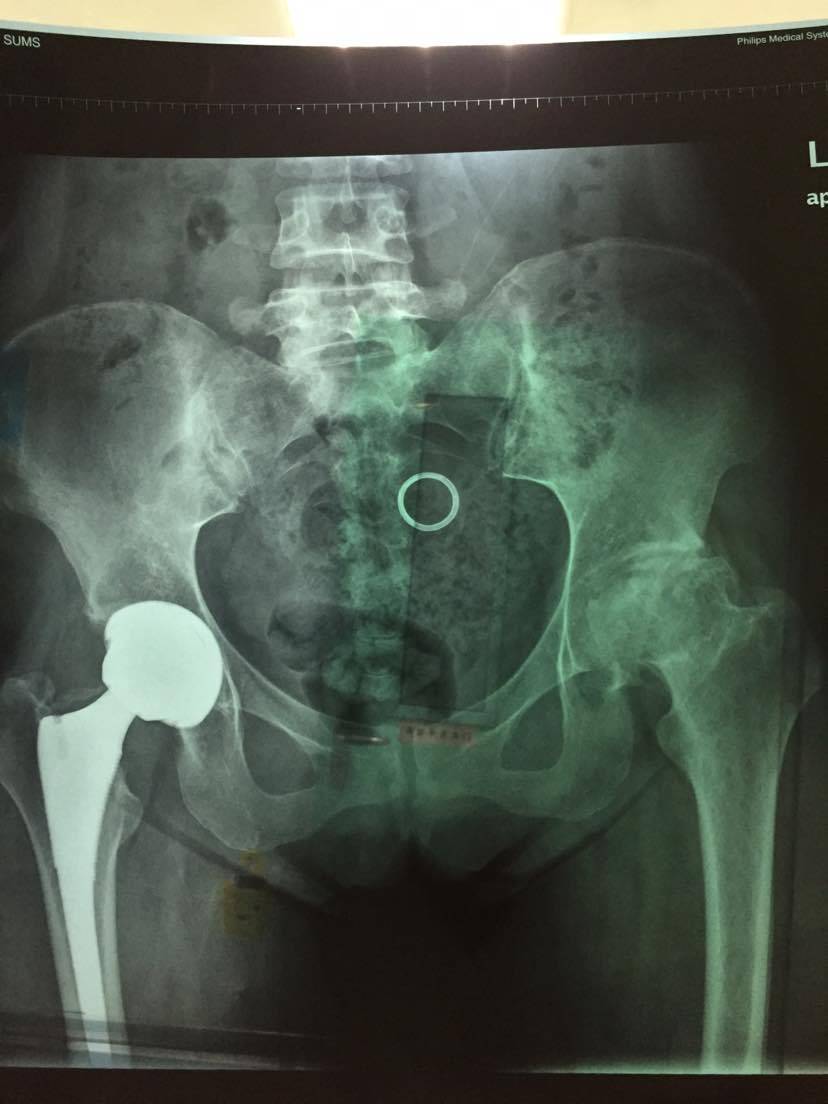

21天行动计划之三,髋关节置换住院第三天

早上教授过来巡查,昨天检查的结果都出来了。发两张重点的出来,自己身体的一部分,学着多了解一点,做什么检查都学着去看看。